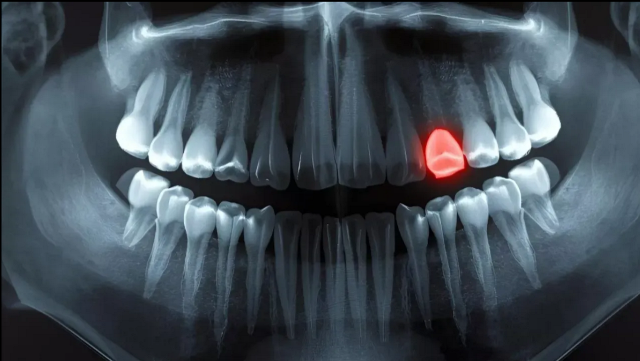

Kemikler kırıldığında kendilerini yeniden büyütebilir, ancak dişler aynı şansa sahip değildir. Bu nedenle dünya genelinde milyonlarca insan dişsizlik sorunu yaşıyor.

Ama dişler kemik değil. Benzer maddelerden yapılmış olsalar da ve insan vücudunun en sert materyali olsalar da, kendilerini onarma ve yeniden büyütme yetenekleri yok. Fakat Japon araştırmacılar, insan dişlerini yeniden büyütmeyi amaçlayan deneysel bir ilaçla ilerliyor. Deneyler Eylül 2024’te başladı.